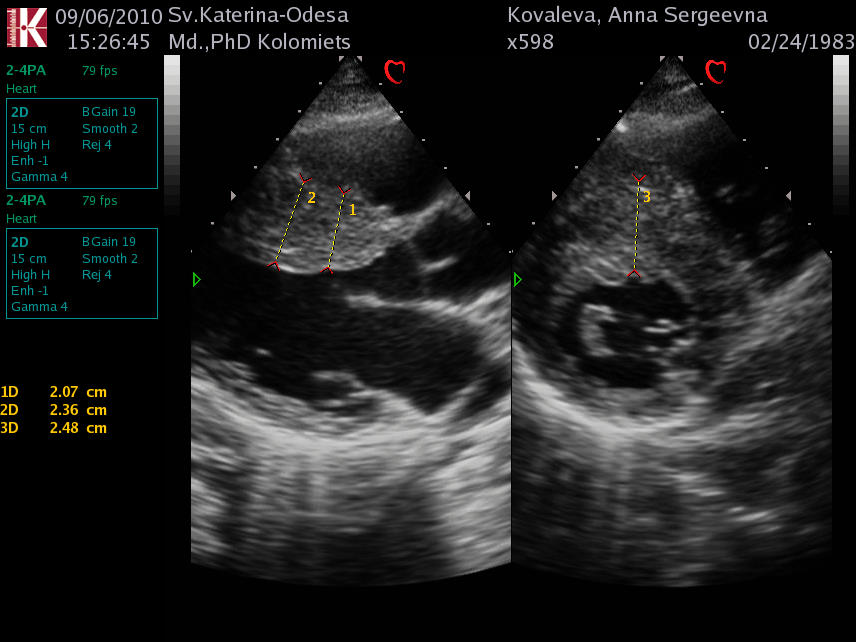

Миксома ЛП